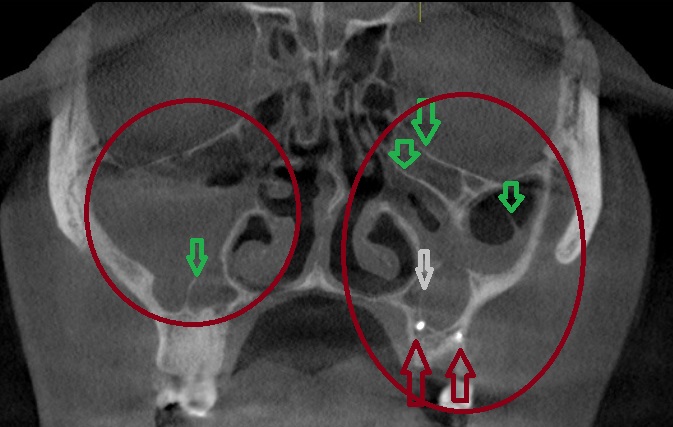

КТ-снимки хронического этмоидита: подробная визуализация